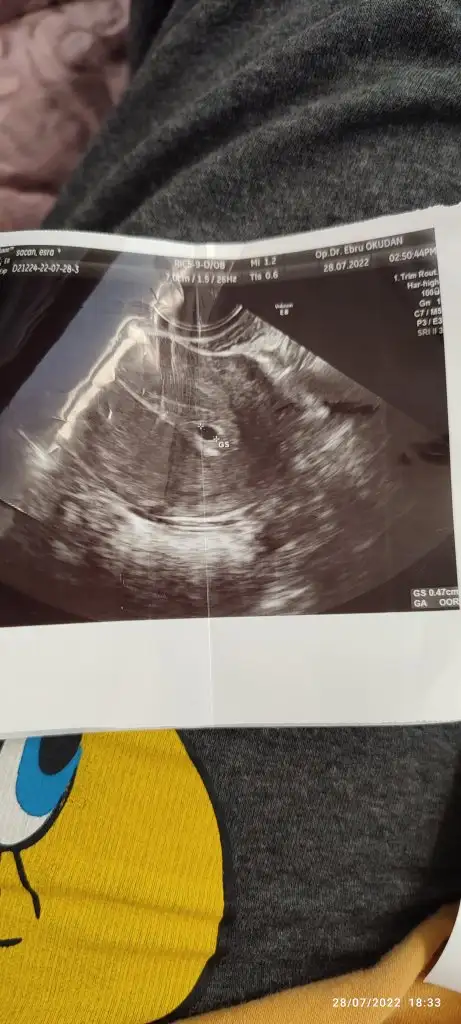

Amin canım. Geçen sene bir kaybım var ama bakalım nasip olursa bu 2. Olucak hamilelik olarakHiç moralini bozma eğer ilk hamileligin olacaksa çok daha rahat oluyor geç olsun güç pasın Allah'ın izniyle![]()